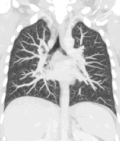

Lungs

[edit]A CT scan can be used for detecting both acute and chronic changes in the lung parenchyma, the tissue of the lungs.[41] It is particularly helpful because normal two-dimensional X-rays do not show such defects. A variety of techniques are used, depending on the suspected abnormality. For evaluation of chronic interstitial processes such as emphysema, and fibrosis,[42] thin sections with high spatial frequency reconstructions are used; often scans are performed both on inspiration and expiration. This special technique is called high resolution CT that produces a sampling of the lung, and not continuous images.[43]

Bronchial wall thickening can be seen on lung CTs and generally (but not always) implies inflammation of the bronchi.[44]

An incidentally found nodule in the absence of symptoms (sometimes referred to as an incidentaloma) may raise concerns that it might represent a tumor, either benign or malignant.[45] Perhaps persuaded by fear, patients and doctors sometimes agree to an intensive schedule of CT scans, sometimes up to every three months and beyond the recommended guidelines, in an attempt to do surveillance on the nodules.[46] However, established guidelines advise that patients without a prior history of cancer and whose solid nodules have not grown over a two-year period are unlikely to have any malignant cancer.[46] For this reason, and because no research provides supporting evidence that intensive surveillance gives better outcomes, and because of risks associated with having CT scans, patients should not receive CT screening in excess of those recommended by established guidelines.[46]